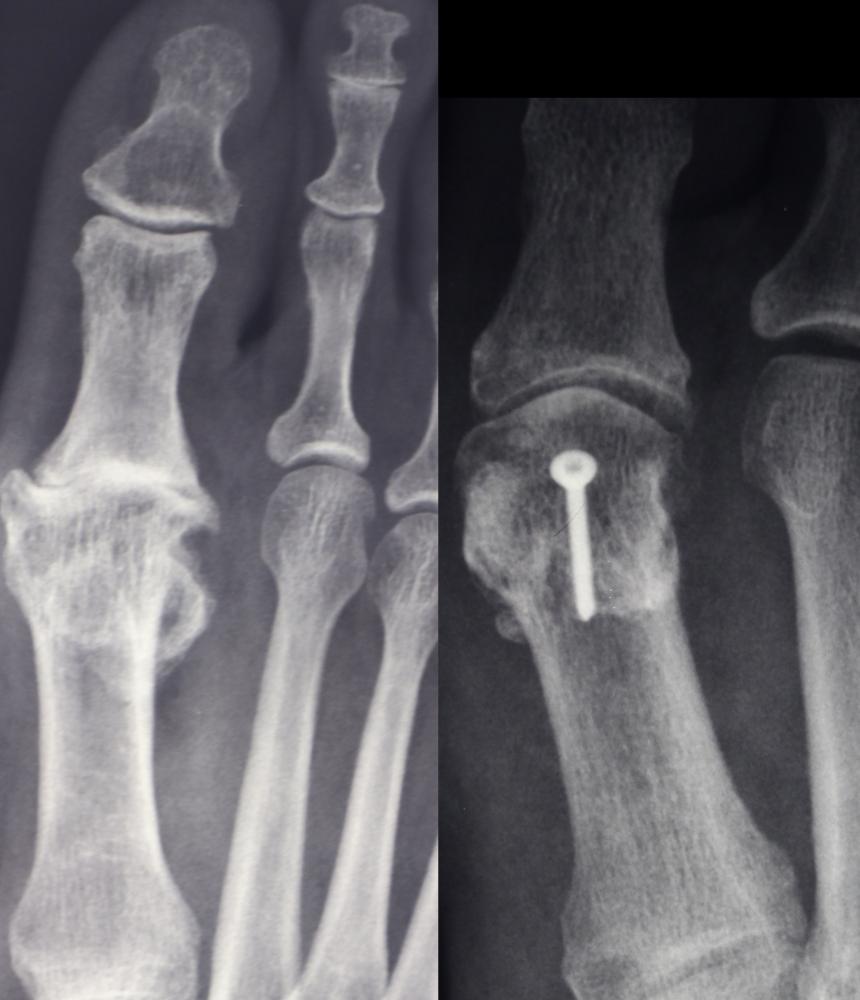

Das Röntgenbild links zeigt einen ausgeprägten Hallux rigidus am rechten Fuß vor der Operation: Der Gelenkspalt im Großzehengrundgelenk ist deutlich verschmälert, die Gelenkflächen sind unregelmäßig, und es zeigen sich dorsale Osteophyten, das sind typische Zeichen einer Arthrose im Großzehengrundgelenk.

Das Röntgenbild rechts zeigt den Zustand des Fußes nach der Hallux rigidus Operation. Hier wurde eine Cheilektomie durchgeführt: Die störenden Knochenausziehungen wurden abgetragen, um den Bewegungsumfang des Großzehengrundgelenks wieder zu verbessern und die Schmerzen zu reduzieren. Zusätzlich erkennt man eine kleine Schraube im Bereich des Metatarsalköpfchens, eine gelenkerhaltende knöcherne Maßnahme, mit der die Biomechanik des Großzehengelenks optimiert wurde.“

Links: Hallux rigidus vor OP, Arthrose im Großzehengrundgelenk Rechts: Hallux rigidus nach OP, deutlich verbessertes Großzehengrundgelenk